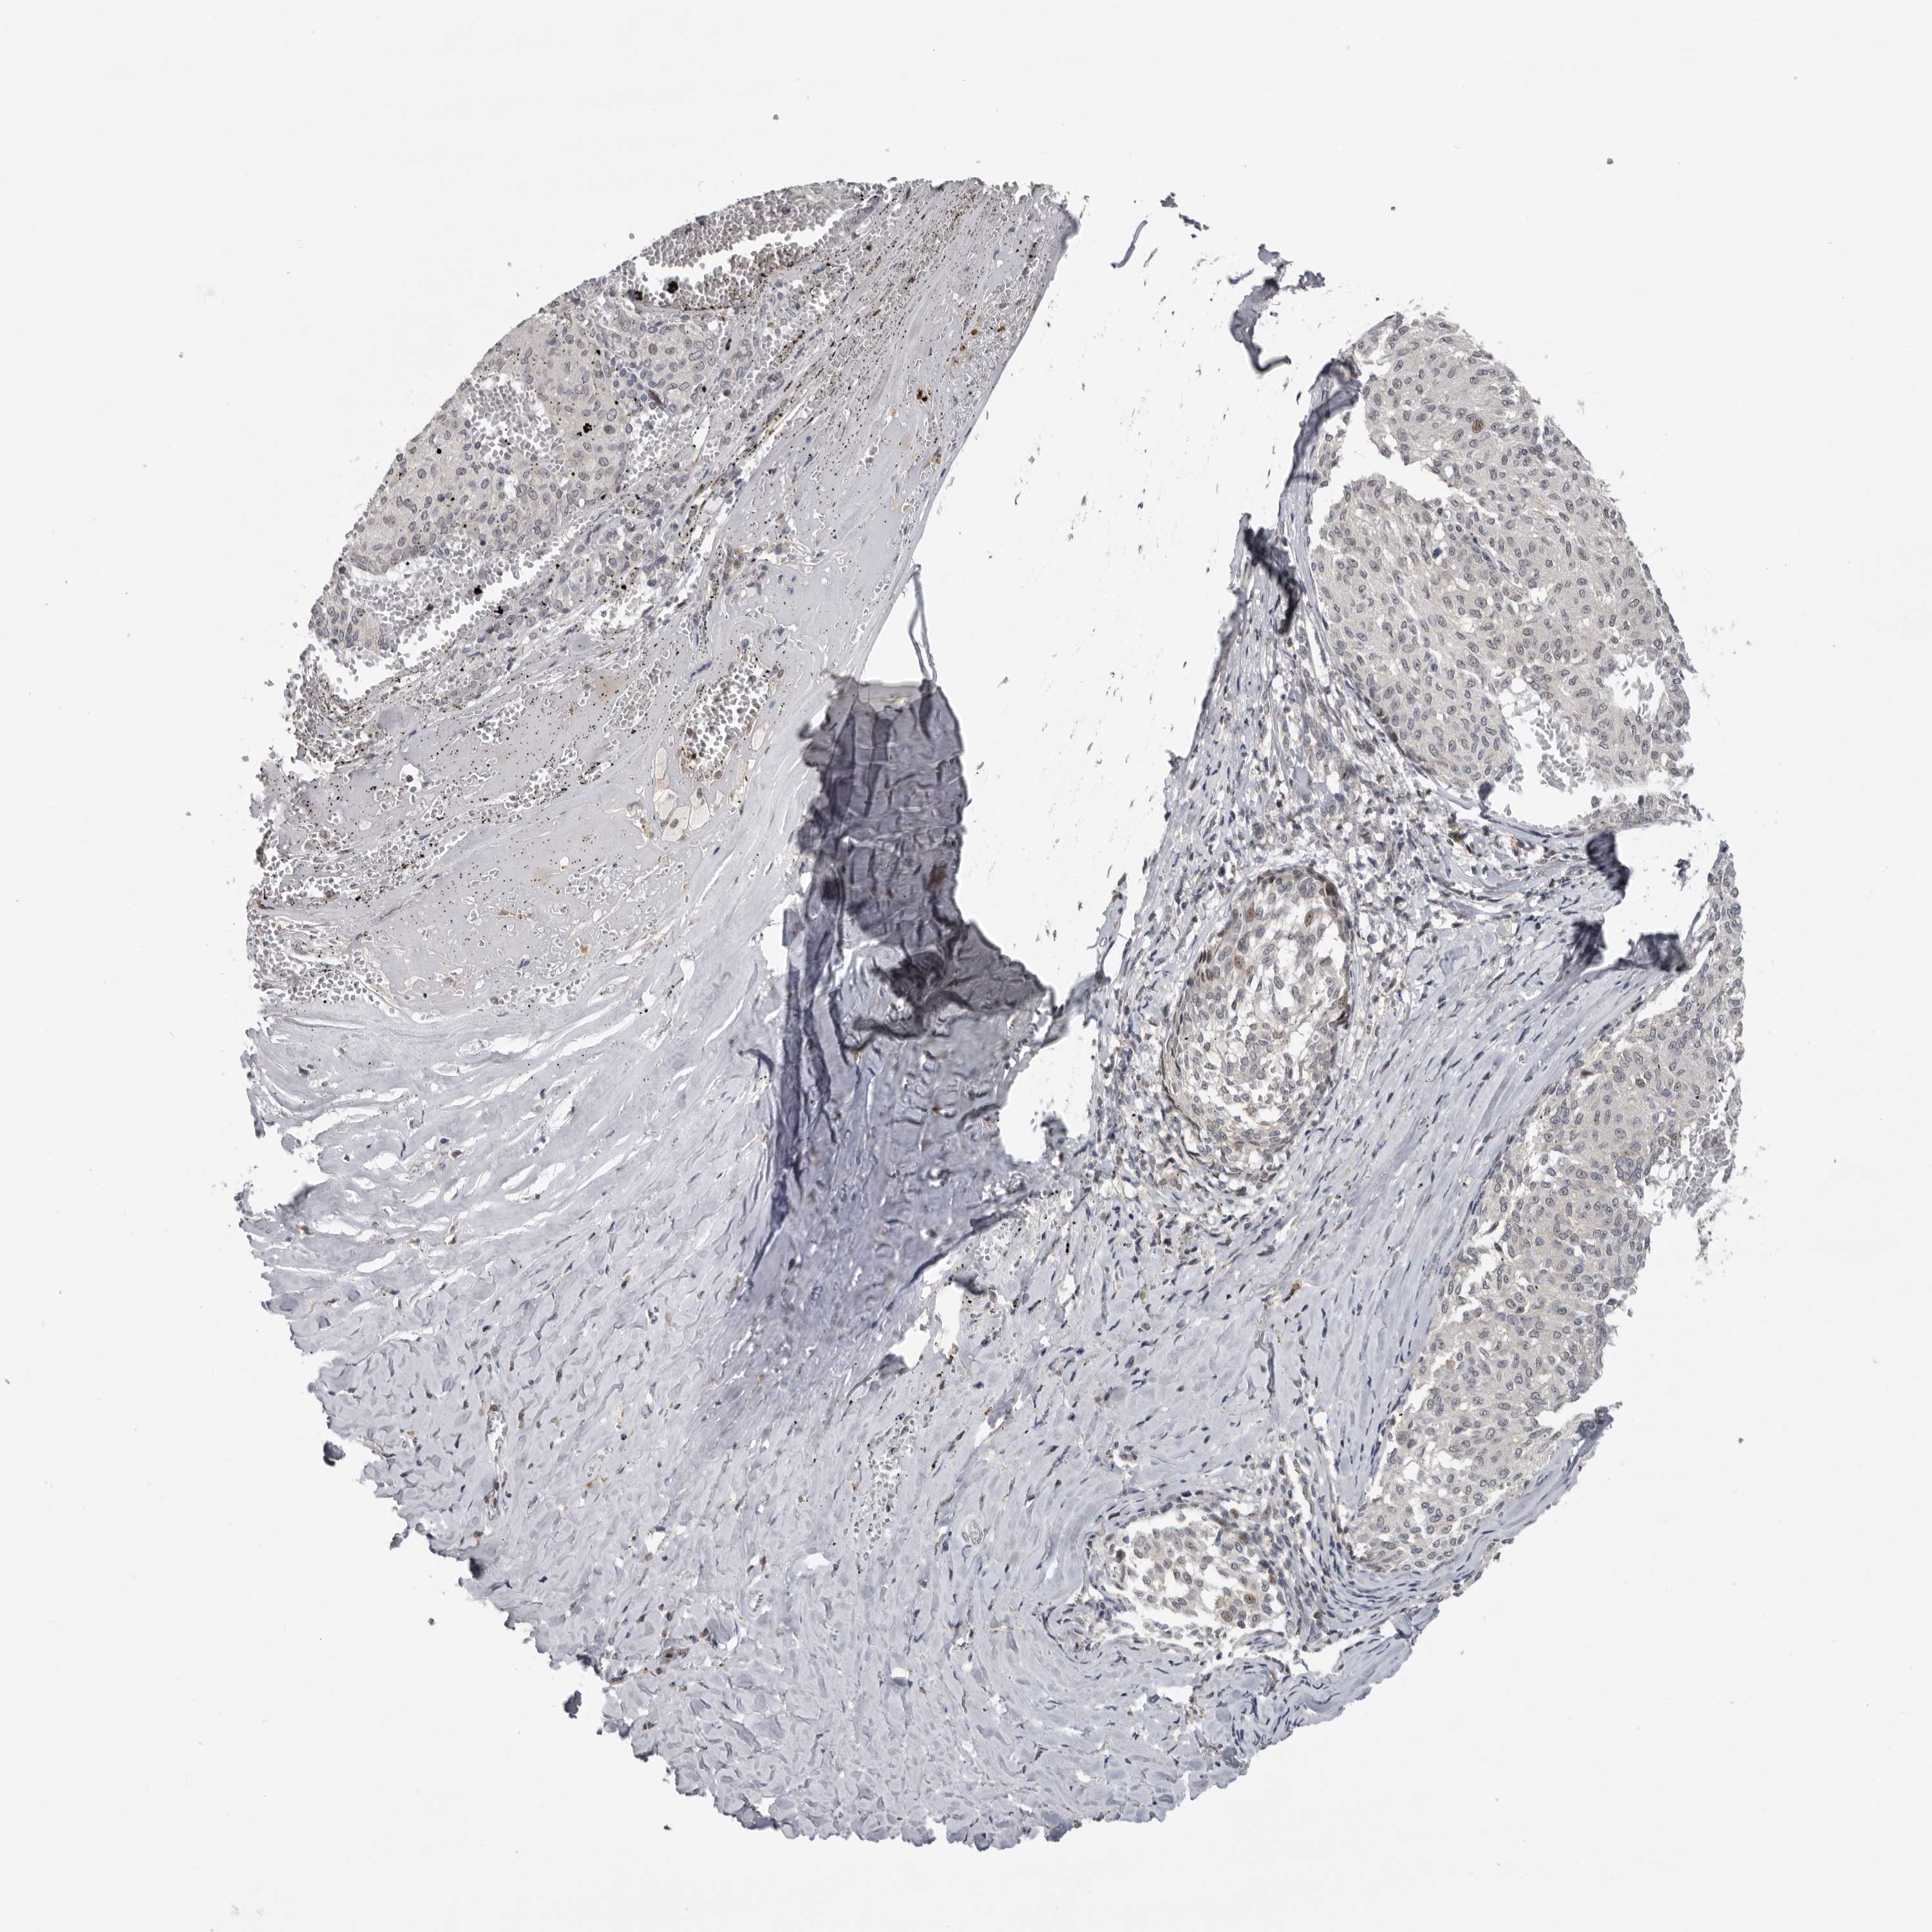

MELANOMA - Protein expressioni

A mouse-over function shows sample information and annotation data. Click on an image to view it in a full screen mode. Samples can be filtered based on level of antibody staining by selecting one or several of the following categories: high, medium, low and not detected. The assay and annotation is described here.

Note that samples used for immunohistochemistry by the Human Protein Atlas do not correspond to samples in the TCGA dataset.

Antibody stainingi

Antibody staining in the annotated cell types in the current human tissue is reported as not detected, low, medium, or high, based on conventional immunohistochemistry profiling in selected tissues. This score is based on the combination of the staining intensity and fraction of stained cells.

Each image is clickable and will lead to virtual microscopy that enables deeper exploration of all samples and also displays staining intensity scores, fraction scores and subcellular localization as well as patient and tissue information for each sample.

Antibody HPA023081

Antibody HPA023103

Antibody HPA024795

Staining

High

Medium

Low

Not detected

Intensity

Strong

Moderate

Weak

Negative

Quantity

>75%

75%-25%

<25%

None

Location

Nuclear

Cytoplasmic/membranous

Cytoplasmic/membranous,nuclear

Malignant melanoma, NOS

Malignant melanoma, Metastatic site